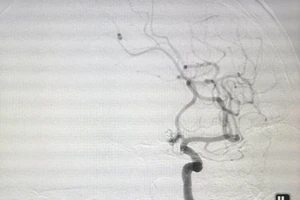

Cứu kịp thời bệnh nhân bị phình động mạch vị tá tràng hiếm gặp